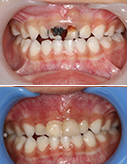

18岁少女矫正结束,一切刚刚好

少女牙齿整齐,笑容更显可爱

矫正牙齿不容易,矫正完成更珍惜